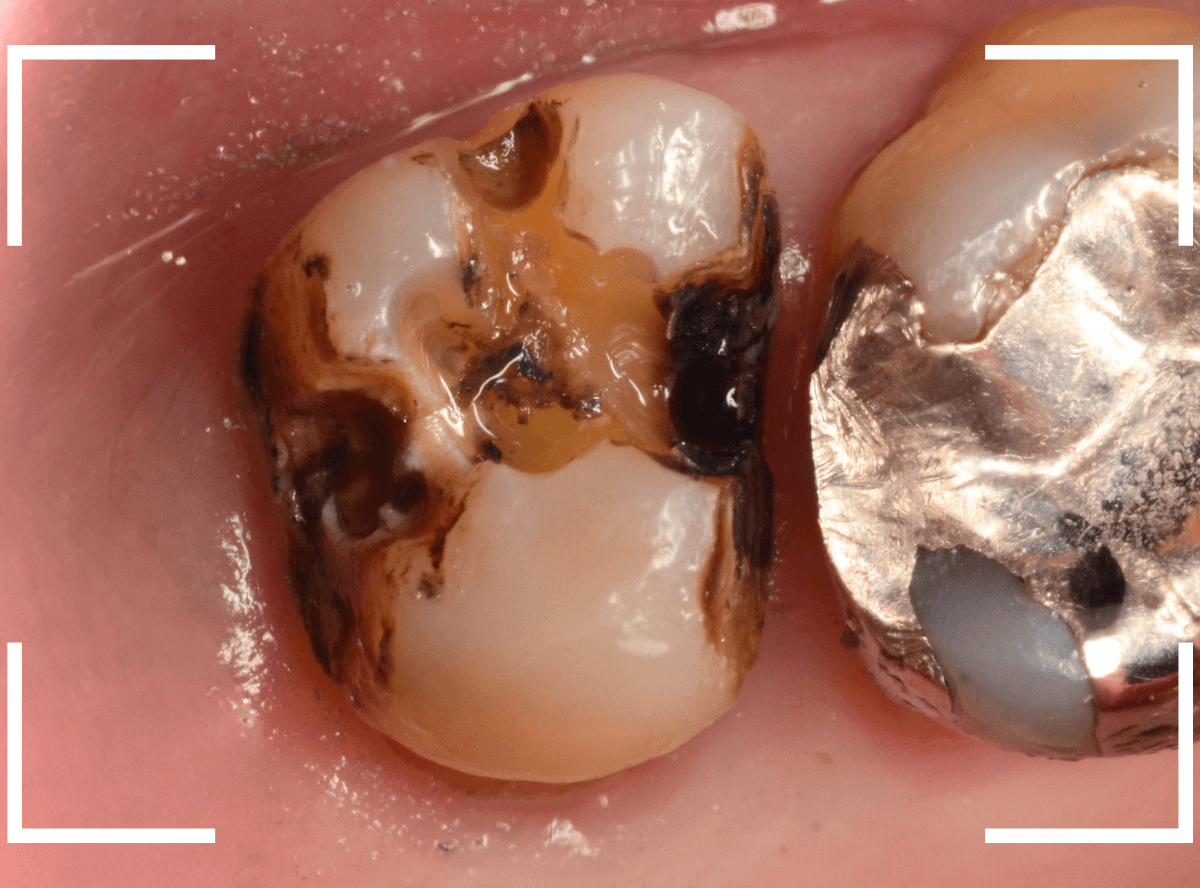

中のお薬も慎重に外して虫歯を除去します。

虫歯が深く、歯肉の下まで浸食していましたので、歯肉を部分切除し、虫歯を全て除去したところで、奇跡的に神経スレスレの状態でとどまっていました。

何とも言えませんが、神経を残せる可能性が出てきました。

虫歯が神経まで達していなくても、治療前から自発痛(何もしなくても痛い)があれば、神経をとらなければいけません。

今回は、そこまでの症状がありませんでしたので、患者さんと相談の上、神経を取らずに残す方法で様子を見る事になりました。